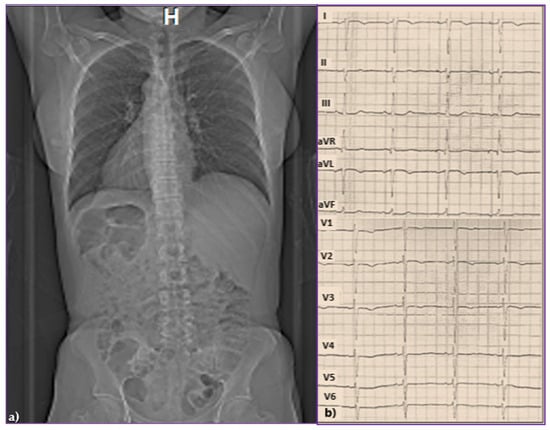

Background: Since the study of Lev and Thaemert in 1973, little has been published concerning the overall arrangement of the murine conduction tissues, in particular with relation to gross anatomical landmarks. We recently emphasised the potential va...